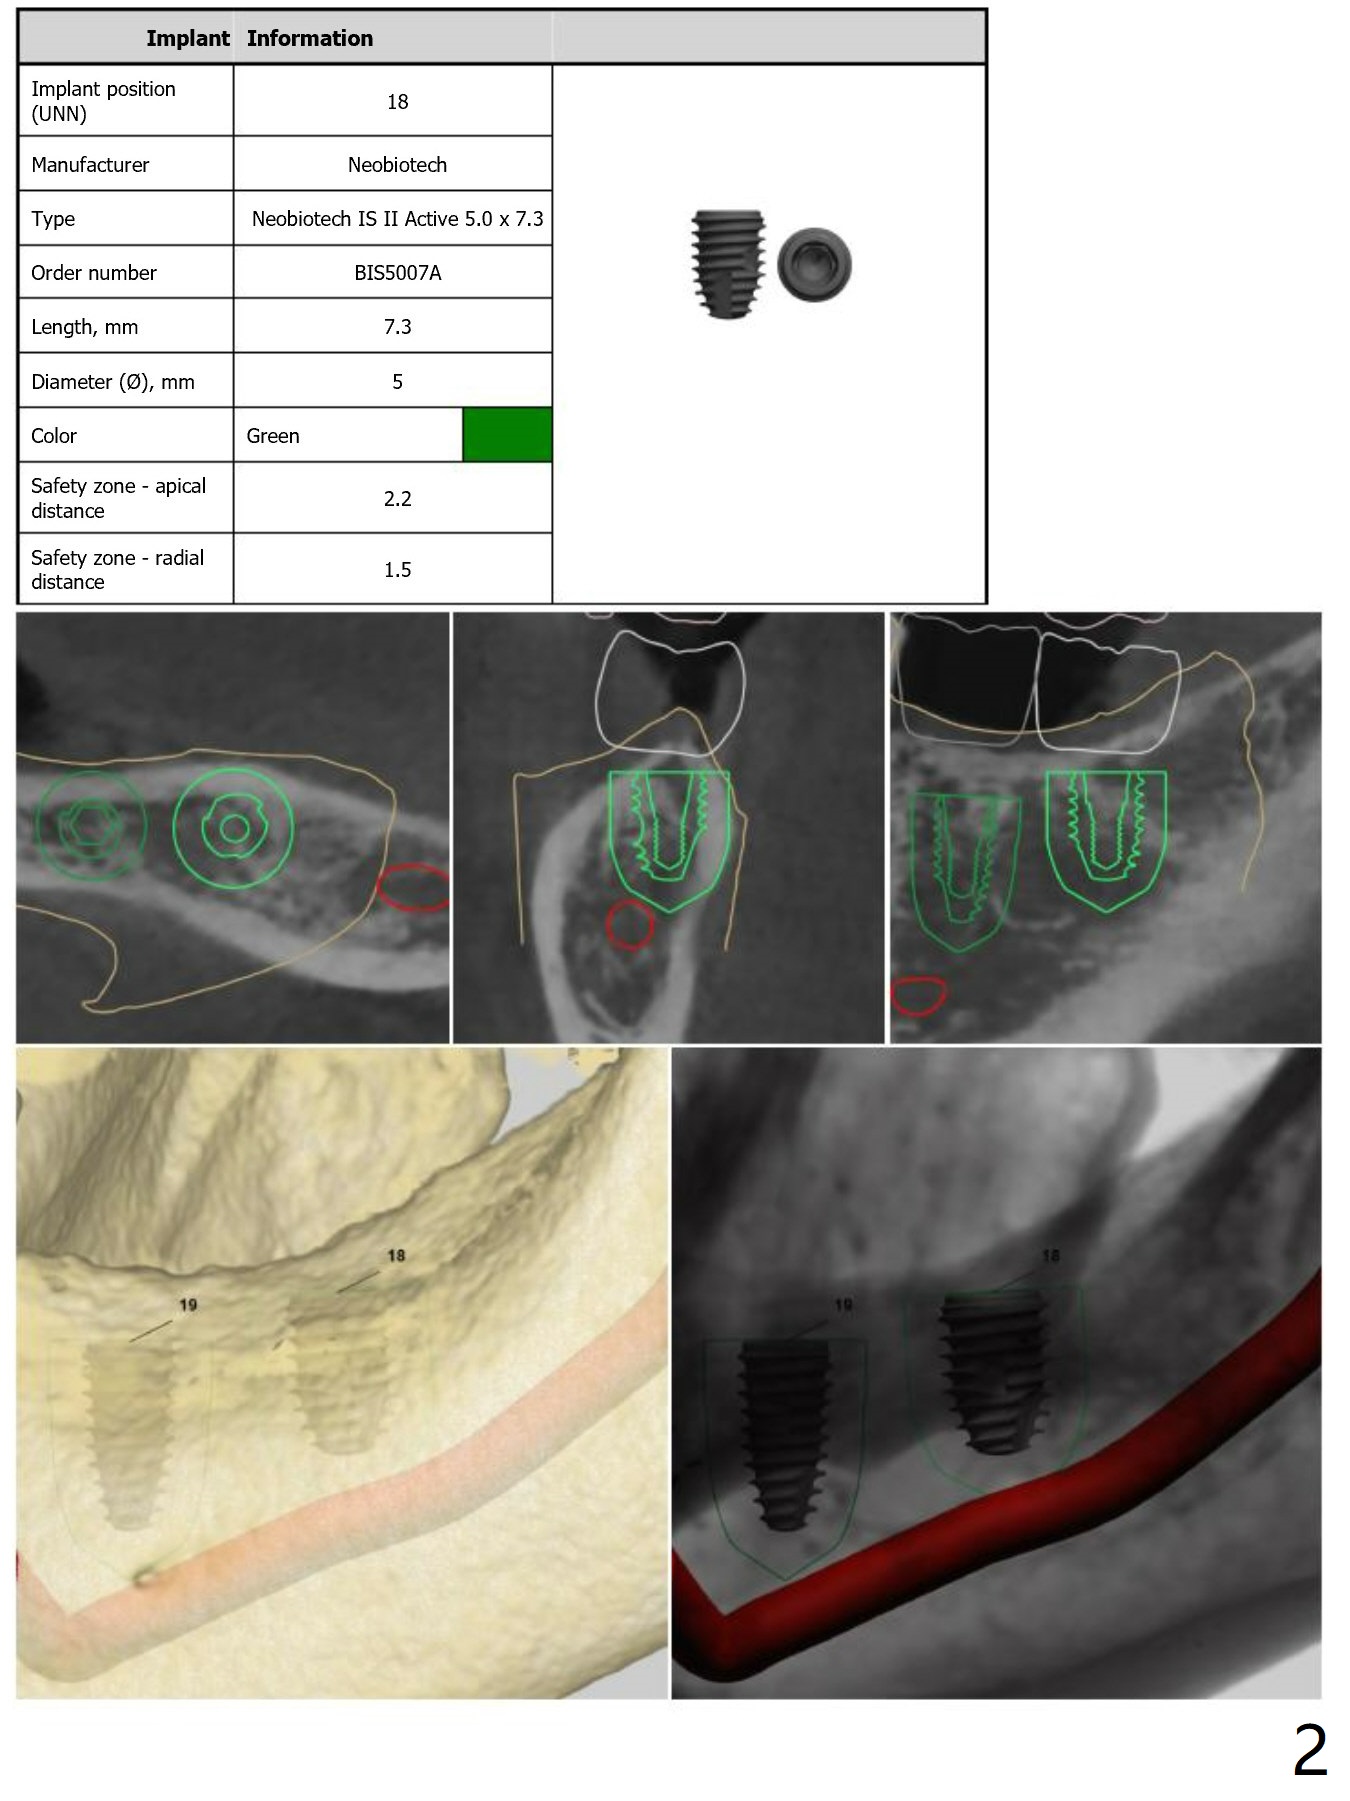

Fixture Anchor Pin at #18

Return to Lower Molar Immediate Implant Armaments  Placement